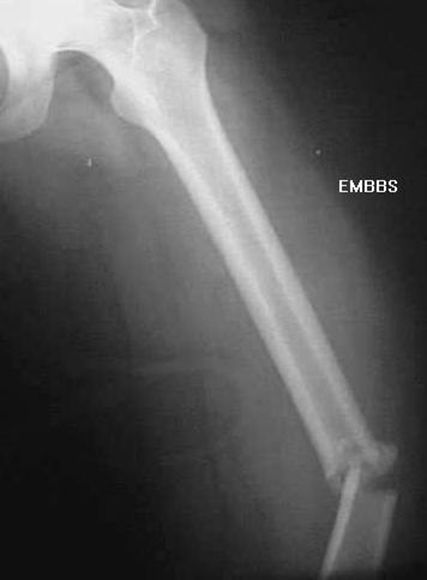

股骨干骨折

疼痛科怎么理疗疼痛科医生、康复理疗科医生、针刀针灸医生应掌握的常见骨科疾病X光片_https://www.jmylbn.com_新闻资讯_第32张